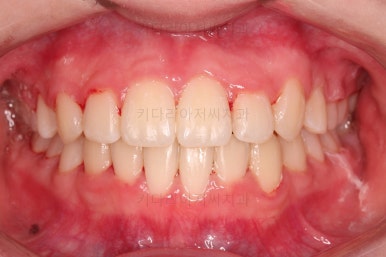

덧니도 개선되었고 가지런한 느낌도 좋네요.

교합도 좋고, 평행하지 않던 느낌도 많이 좋아졌습니다.

전후 사진을 보여드리겠습니다.

많은 부분이 좋아졌고요.

웃을 때 기울어져 보이던 치열의 모습도 좋아졌습니다.